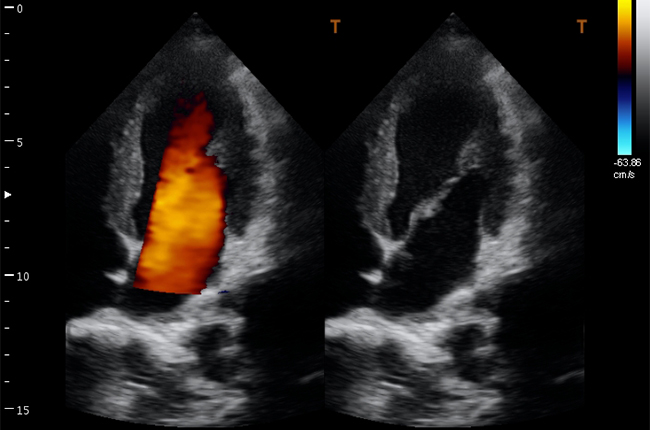

Кольорове допплерівське картування

Енергетичний допплерівський режим

CW - постійно-хвильовий допплер

Кардіологія